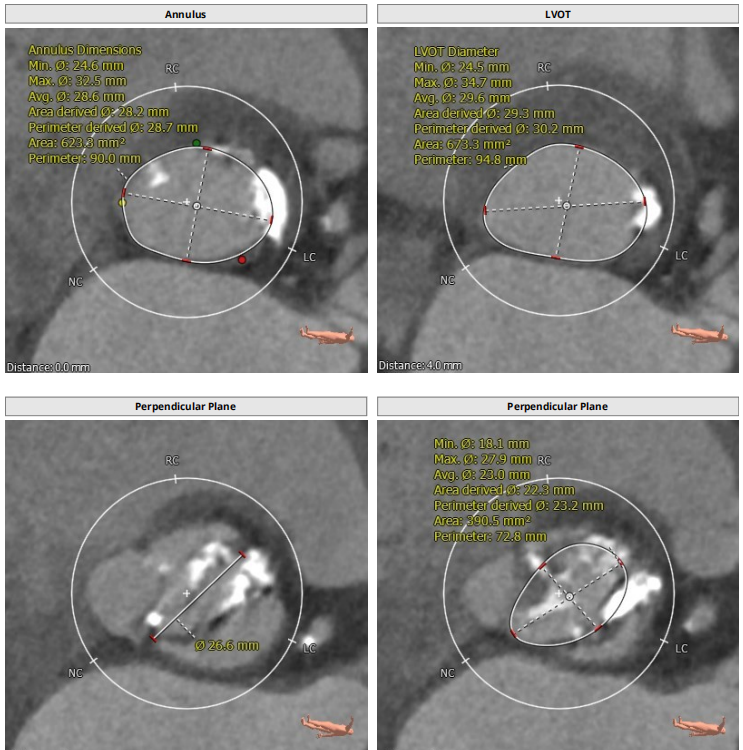

解剖上,这个患者虽然是右无融合的二叶瓣,但是右窦发育较小,形态上接近0型二叶瓣,瓣上钙化中,且集中在左窦,接近左右瓣叶联合部。瓣环及流出道平面较大,而瓣上结构较小,瓣叶联合部距离只有26,这种情况下只能考虑根据瓣上结构进行选择瓣膜。目标瓣膜为26号,为了避免破坏瓣上结构,我们选择26瓣膜的下限20号瓣膜进行与扩张。因为主动脉弓和升主动脉角度问题,没有选择plus。20球囊扩张可以看到左窦钙化很硬,右无联合可以推开,没有反流,故选择26号瓣膜,高位释放。释放后瓣膜下滑到标准位,有明显的腰,故用20球囊进行后扩展。最后造影虽然有中度瓣周漏,但是考虑患者狭窄解除,且升主动脉人工血管限制了瓣膜的流出端,未再行瓣中瓣。术中撤除ECMO,辅助循环约1小时。

患者既往行全升主人工血管置换,为type1型二叶瓣畸形患者,瓣环28.7,左室流出道30.2,二叶瓣鱼嘴短径为26.6,重度钙化,左右冠分别为12.7与15.1,STJ30.8,升主均径人工血管为27.7,患者EF值极低,心功能极差,遂行ECMO辅助下TAVR术式。

根部解剖: